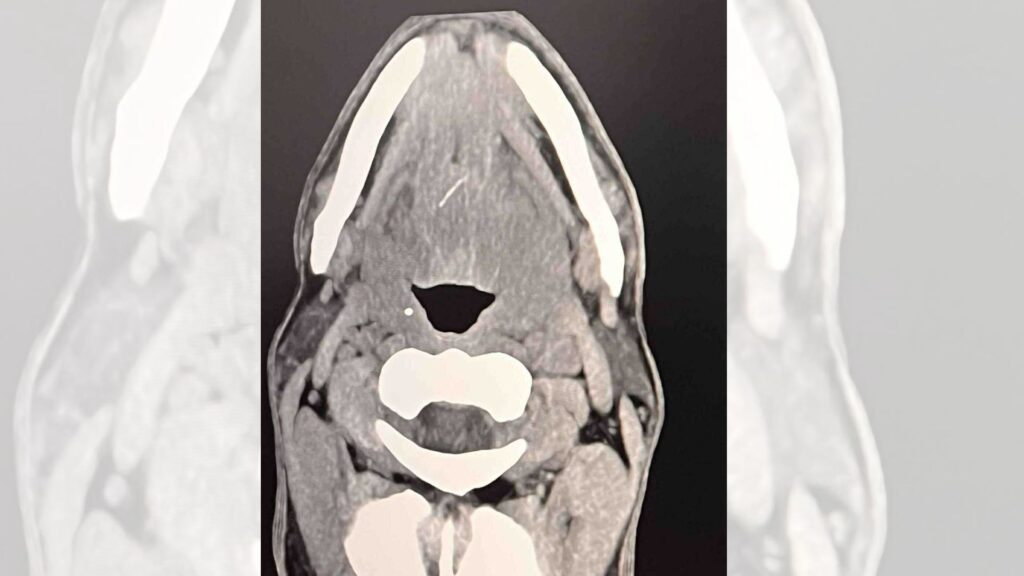

разкрива тънка 12-милиметрова конструкция, наподобяваща рибена кост, заседнала надълбоко във вътрешните мускули на езика. Образните проучвания посочили и съществуване на цирей в съседство, който създавал риск от съществени затруднения, в това число засягане на дихателните пътища.

Снимка УМБАЛ Каспела